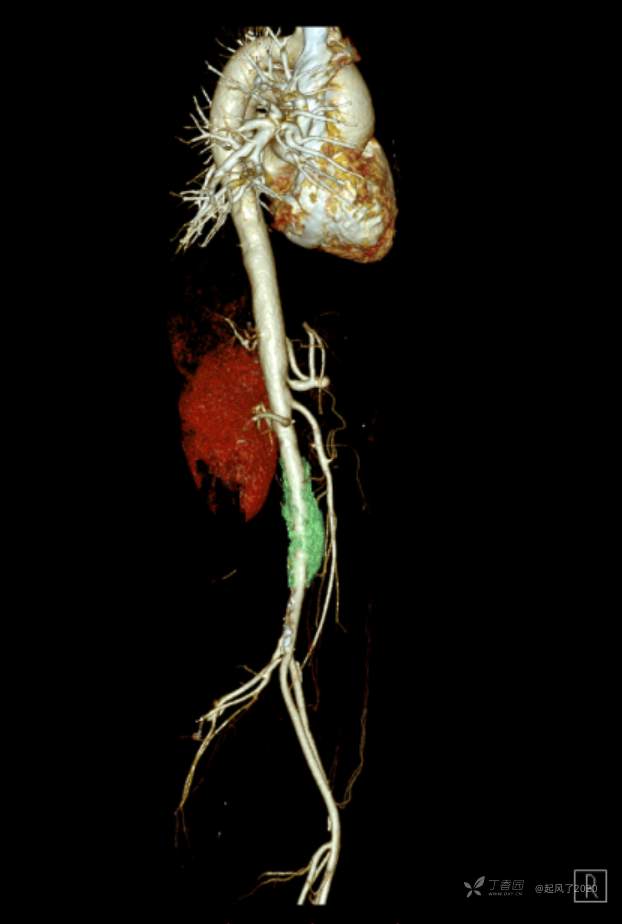

求助 | 女,61岁,下腹部、腰及双髋关节隐痛1月余

II型糖尿病10年余,既往饮食控制血糖在7~8左右,今年1月份开始服用二甲双胍;2009年4月因“子宫肌瘤、双侧输卵管慢性炎症”行子宫及附件切除术;2021年1月体检发现双侧甲状腺多发结节,较大者12*7mm;高血脂10余年,近1月开始规律服药,控制不理想;无高血压